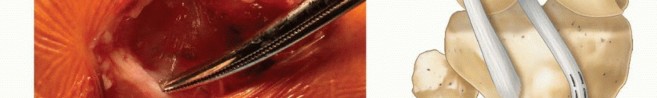

The anterior and posterior borders of the iliotibial band are incised and the incisions carried proximally under the skin using curved meniscotomes ( TECH FIG 1A ).

The iliotibial band is detached proximally under the skin using a curved meniscotome or an open tendon stripper. Alternatively, a counterincision can be made at the upper thigh to release the tendon.

Dissection is performed distally to separate the iliotibial band from the joint capsule and from the lateral patellar retinaculum ( TECH FIG 1B ).

The iliotibial band is left attached distally at the tubercle of Gerdy ( TECH FIG 1C ).

The free proximal end of the iliotibial band is tubularized with a no. 5 Ethibond whipstitch and wrapped in a moist sponge until needed later. -

TECH FIG 1 • Harvest of iliotibial band graft for physeal-sparing ACL reconstruction. The anterior and posterior aspects of the iliotibial band are identified through a laterally based incision at the knee. A. A meniscotome or an open tendon stripper is then used to harvest the proximal aspect of the graft. B. The graft is then freed distally. C. The free proximal aspect of the graft is tubularized and left attached distally to the tubercle of Gerdy. (A,B: From Kocher MS, Weiss JM. ACL reconstruction in the skeletally

immature patient. In: Tolo VT, Scaggs DL, eds. Master Techniques in Orthopaedic Surgery: Pediatrics. Philadelphia: Lippincott Williams & Wilkins, 2008:277-287.)